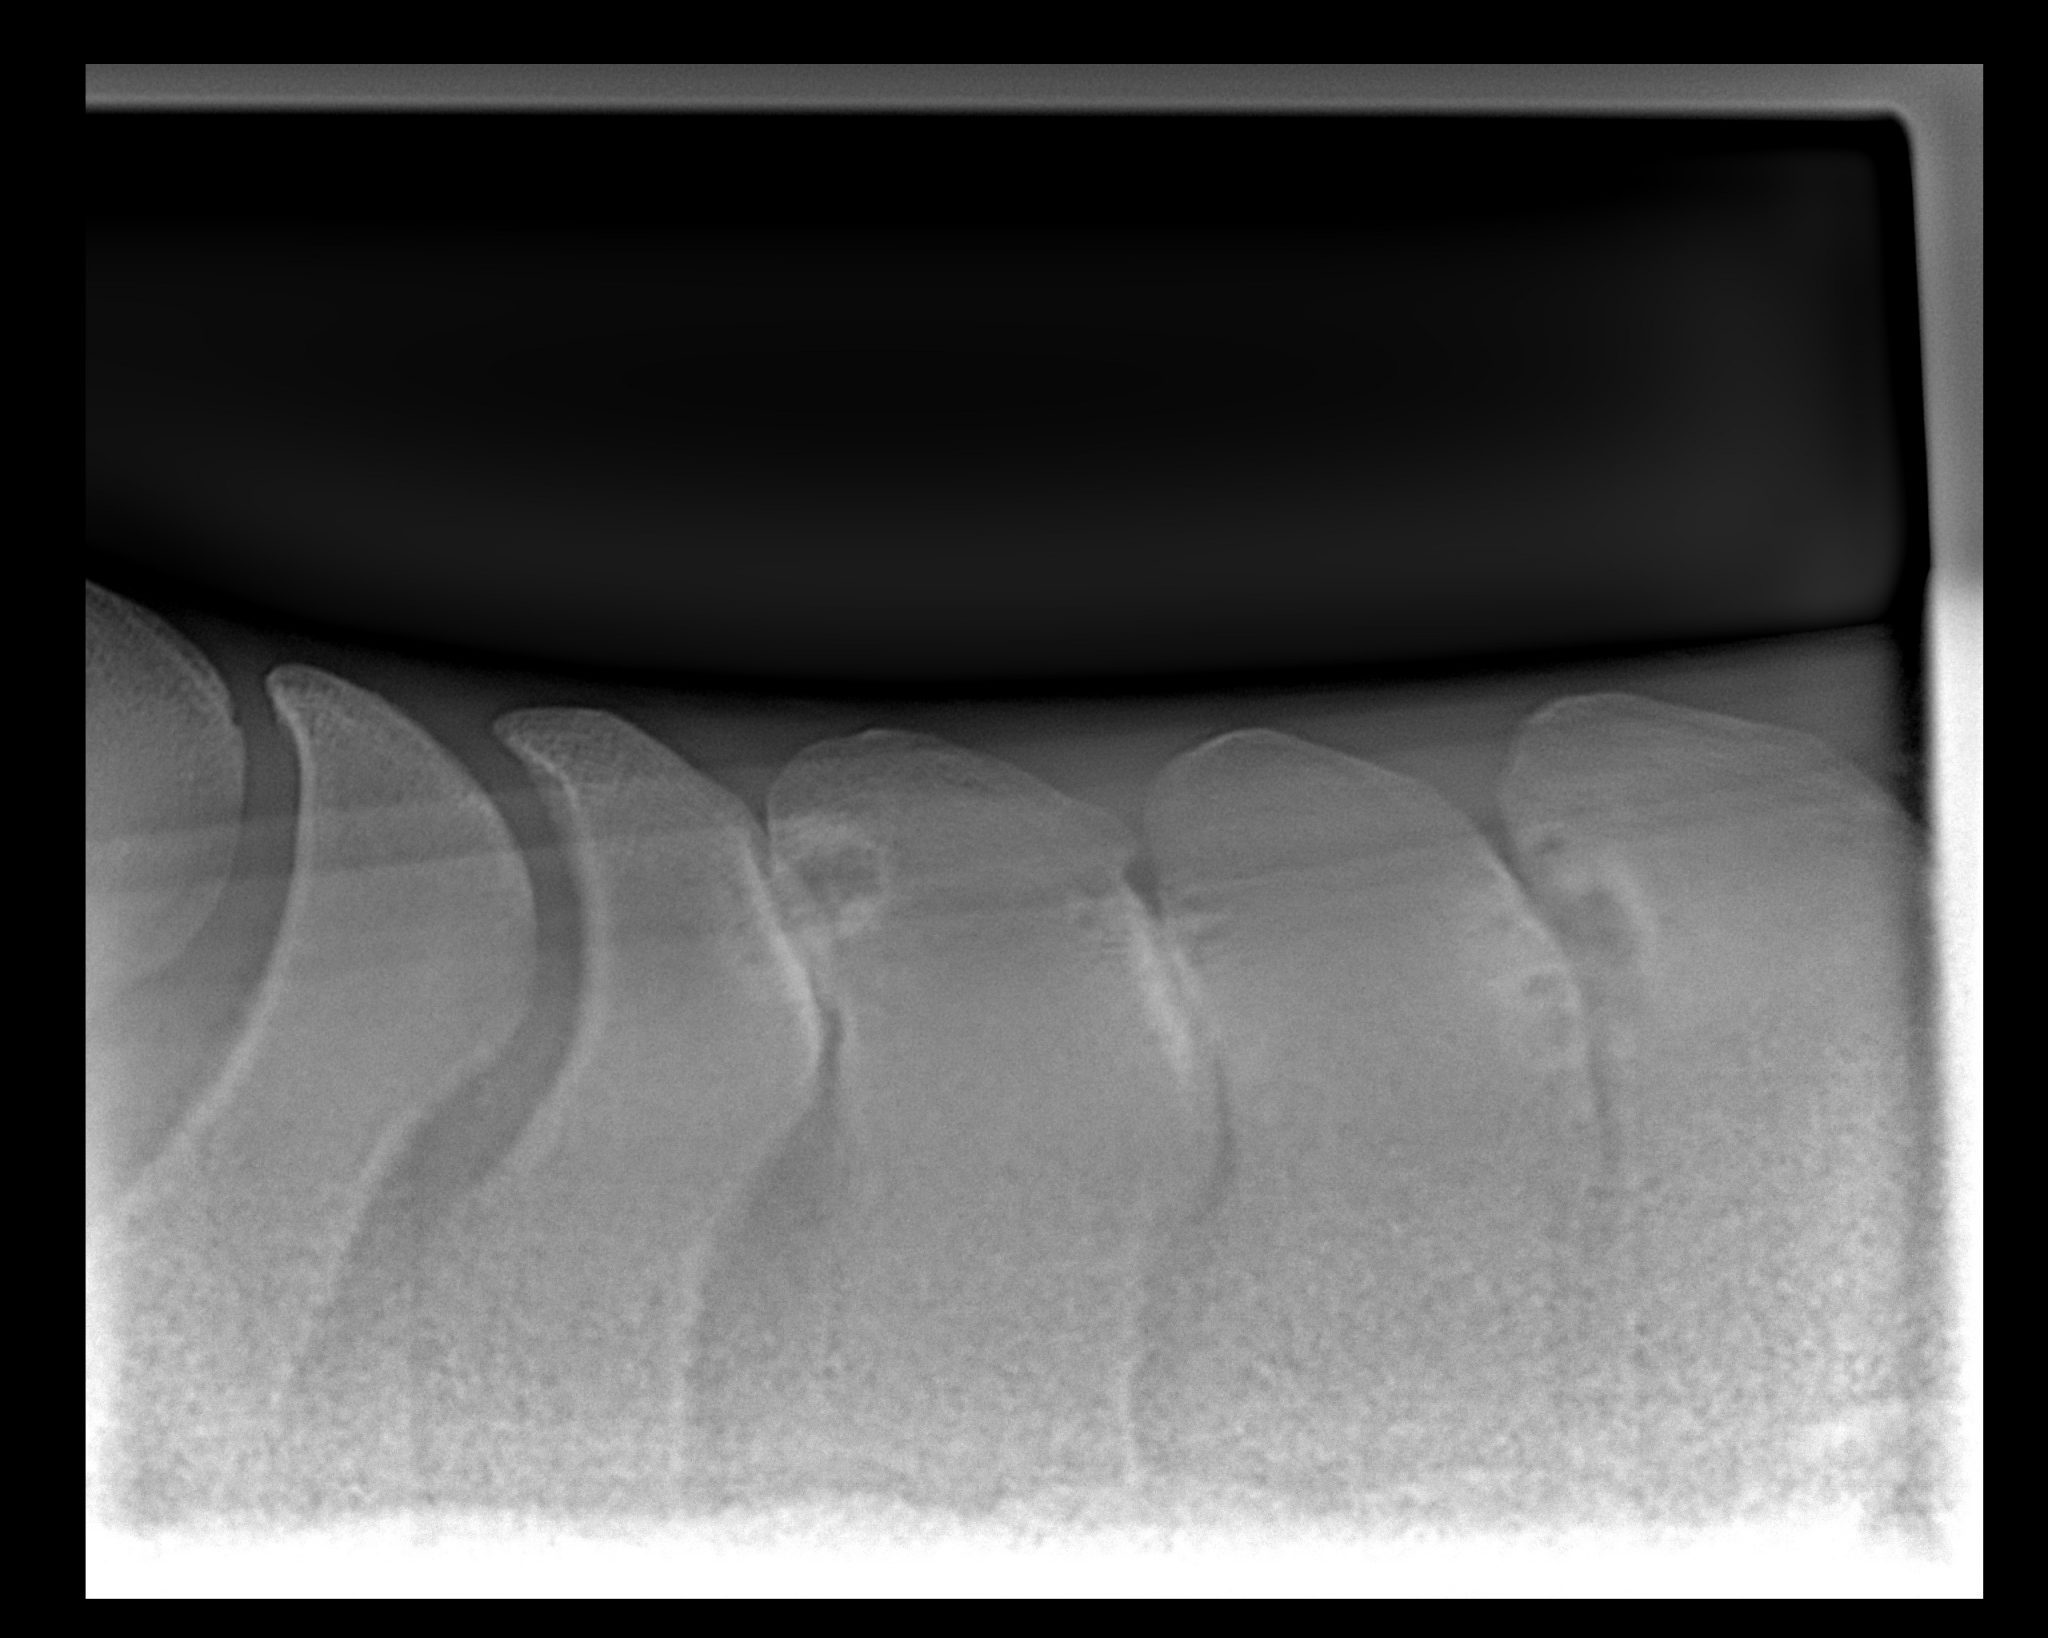

Imaging - X-ray and Ultrasound

In order to isolate and eliminate pain from a diagnostic approach we are able to infiltrate local anaesthetic around nerves and within joints – which “blocks” or removes the pain sensation. If a patient's gait then improves after this technique is done we know roughly the source of the pain. At this point we often progress onto imaging the area with x-ray or ultrasound to specifically identify the injured / changed structure(s). This then allows us to construct a treatment plan.